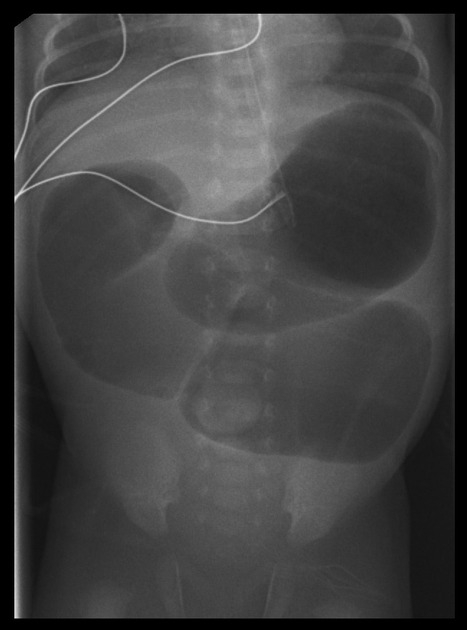

- Abdominal X-ray shows air in the stomach, and proximal duodenum (double-bubble sign) with no distal bowel gas.